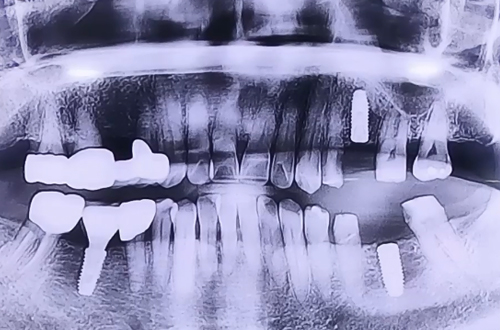

AFTER

브릿지 제거 후 위아래 남은 양옆의 치아들은 보철로 이를 둘러 씌워주고 임플란트 치료를 마무리해드렸습니다.

추후 이플란트가 주변 뼈들과 단단하게 굳고 나면 임플란트 위쪽으로 어금니를 예쁘게 제작해 드릴 예정입니다.

3개월 후 보철이 완성된 이후 다음 진료일지로 찾아뵙도록 하겠습니다!